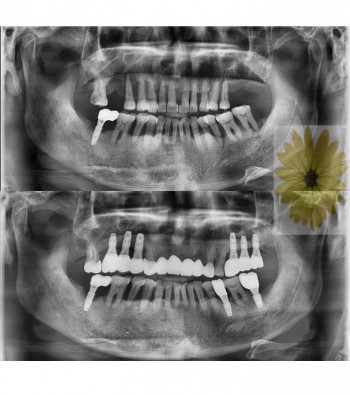

민들레치과 치료 전후사례